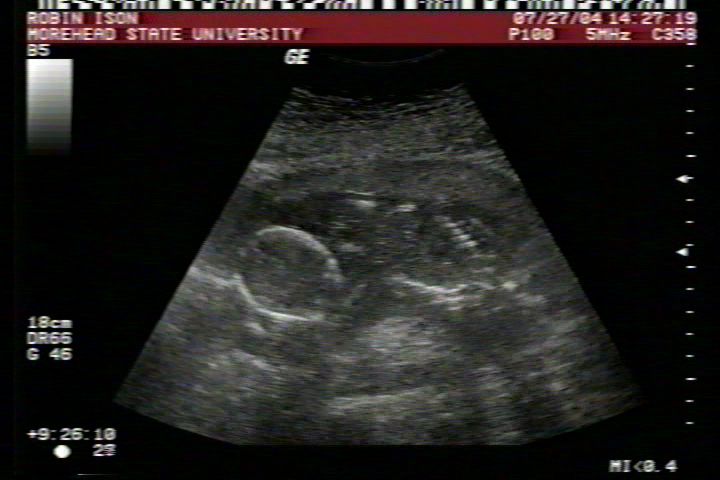

Pictures from Ultrasound at 17 weeks.